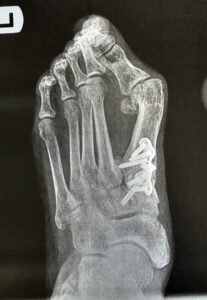

There is a lot of media these days about doing minimal incision bunion surgery, but patients should review our bunion and minimally invasive surgery services before choosing a procedure. Do not be a victim of the hardware doctor, and meet Dr. Singh to learn about his approach to true minimal incision correction. They think this is minimal incision. They make a small incision. Then they insert these large screws. Sometimes they insert screws and plates. This is not minimal incision. This is totally criminal. Who would want to have such a procedure done. Look at the second picture. This is a bunion. Who would want such correction done to them. Look at the third picture. How do you think the bunion is going to even heal? Stay away from the surgeons that profess minimal incision surgery using these types of hardware. Do yourself a favor and educate yourself.